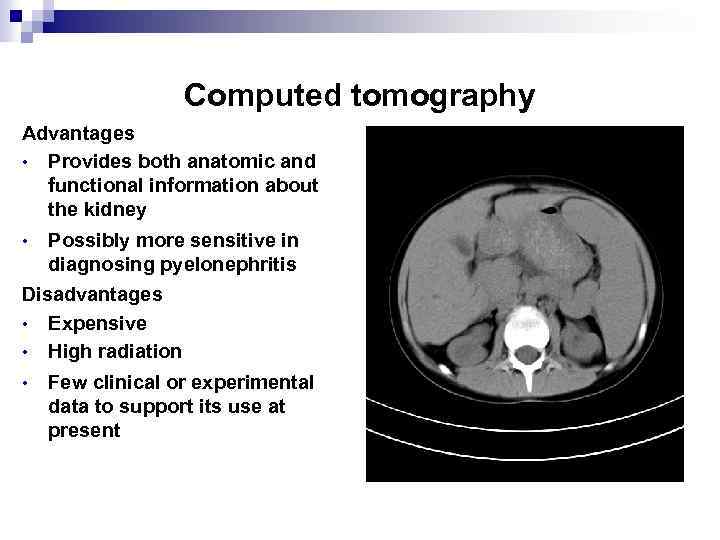

Computed tomography Advantages • Provides both anatomic and functional information about the kidney Possibly more sensitive in diagnosing pyelonephritis Disadvantages • Expensive • High radiation • • Few clinical or experimental data to support its use at present

Computed tomography Advantages • Provides both anatomic and functional information about the kidney Possibly more sensitive in diagnosing pyelonephritis Disadvantages • Expensive • High radiation • • Few clinical or experimental data to support its use at present